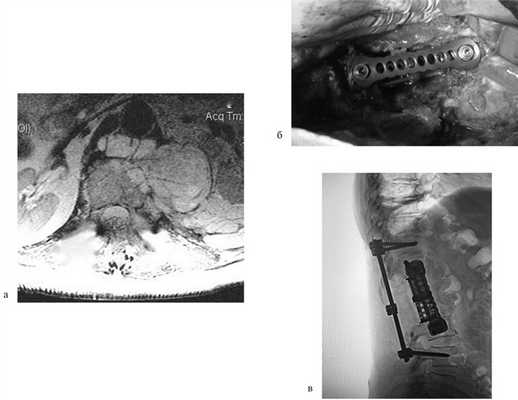

Пациентка Н., 69 лет, поступила в апреле 2016 г. в отделение онкоортопедии МНИОИ им. П.А. Герцена с диагнозом хондросаркома позвонка LII T3N0M0 G1 III стадии. Пациентка самостоятельно не передвигалась из-за выраженного болевого синдрома в проекции поясничного отдела позвоночника. 3 балла по ECOG, 50 баллов по шкале Карновского и 3 балла по Watkins. Парапарез нижних конечностей до 2 баллов. В апреле 2016 г. 1-м этапом выполнена декомпрессивная ламинэктомия позвонков LI—II с задней стабилизацией на уровне позвонков ThXII—LIII. Послеоперационный период без осложнений. Далее в мае того же года выполнен 2-й этап хирургического лечения: корпорэктомия позвонков LI—II с эндопротезированием тел позвонков телескопическим эндопротезом (рис. 3). Пациентка выписана на 9-е сутки после операции, передвигалась самостоятельно без дополнительных средств опоры (1 балл по ECOG, 80 баллов по шкале Карновского, 1 балл по шкале Watkins), рекомендован динамический контроль онколога по месту жительства.

Рис. 3. МРТ-картина до хирургического лечения (а). Тело позвонка LII с признаками деструкции, структура его представлена опухолевой массой размером 87×57×67 мм. Интраоперационная фотография (б), боковой доступ. Установленный телескопический эндопротез тел позвонков LI—II c боковой фиксирующей пластиной. Послеоперационная рентгенограмма поясничного отдела позвоночника (в). Металлоконструкция установлена корректно. Исследование выполнено на 1-е сутки после хирургического лечения.